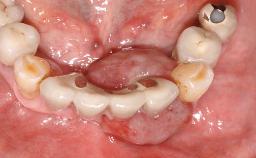

Surgical treatment of a 68-year-old female patient with a distal extension situation in the left mandible. As the CBCT analysis reveals, the bone crest anatomy in the area is not ideal and necessitates an augmentation procedure to achieve a good long-term prognosis for the planned implants and their prostheses.

After the placement of three diameter-reduced two-piece implants the bone is augmented with autologous bone chips and DBBM particles to enlarge the crest volume. The surgery is completed with the application of two membrane layers and primary wound closure.